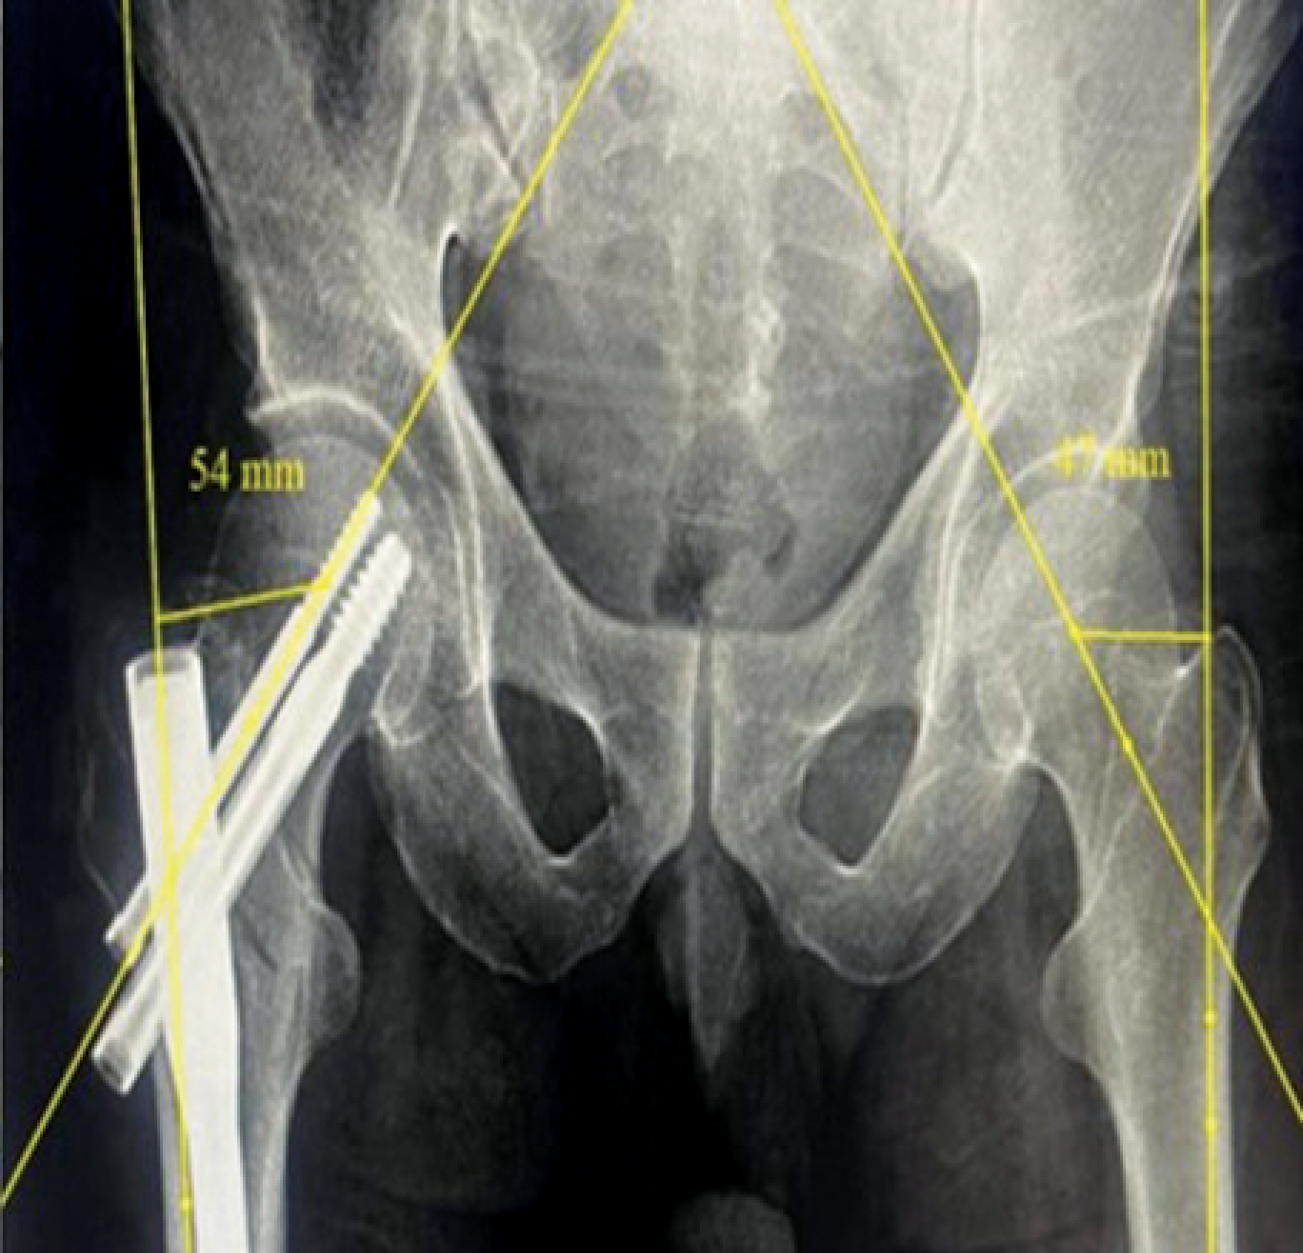

Postoperative evaluation included immediate anteroposterior (AP) and lateral X-rays of the hip. The femoral NSA was determined according to the methodology described by C. K. Boese et al. [10]. This angle was calculated between the axis of the femoral neck and the anatomical axis of the FS. The neck axis was drawn from the femoral head center (HC) to the neck center (NC), the latter defined as the midpoint between points where a circle (centered on the HC) intersected the superior and inferior borders of the femoral neck. The shaft axis was established by connecting central points identified at both proximal and distal segments of the femoral diaphysis [11]. The tip-apex distance (TAD) was calculated as the cumulative length from the screw tip to the apex of the femoral head as seen on both the AP and lateral projections [12]. FS lateralization was assessed by measuring the horizontal distance from the femoral head center to a reference line parallel to the lateral cortex of the femur, comparing the injured side with the contralateral uninjured side [7] (Figures 1, 2).

Figure 1. Neck-shaft angle measurements on an upright pelvis plain X-ray

No significant difference in neck shaft angles was observed postoperatively compared to the contralateral side in either PFN or DHS groups (Table 4, Figures 3, 4).

Figure 3. X-ray of a patient from the DHS group: a — postoperative neck-shaft angle; b — neck-shaft angle of contralateral unaffected side

Figure 4. X-ray of a patient from the PFN group, showing 5 degrees of varus malalignment as compared to the unaffected contralateral side

Figure 7. X-ray of a patient from the PFN group, showing femoral shaft lateralization (uninjured side — 47 mm, injured side — 54 mm)